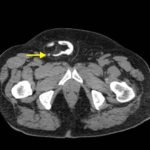

Ultrasound of the right scrotum shows a right inguinal hernia with an air-containing loop of bowel (white arrow) and a non-compressible appendix (yellow arrow). Coronal and axial views of abdomen-pelvis CT show a right inguinal hernia containing a loop of small bowel (white arrow) and appendix (yellow arrow).

In the case presented above, ultrasound and abdomen and pelvis computed tomography (CT) showed an Amyand’s hernia. The patient was taken emergently to surgery, which revealed an incarcerated right inguinal hernia with perforated appendicitis in the hernia sac. The patient underwent an appendectomy and hernia repair, and had no post-surgical complications.

Amyand’s hernia is a form of inguinal hernia characterized by the presence of the appendix in the hernia sac. The hernia may be reducible, incarcerated, or strangulated; and the appendix may be normal, inflamed, or perforated.1 The patient presented above had an incarcerated hernia with no overlying skin changes suggestive of strangulation. Amyand’s hernia accounts for 0.4-1% of all inguinal hernias and 0.1% of all cases of appendicitis.2 It is thought to be due to patency of the processus vaginalis, and as such occurs more frequently in young children.1,2,3 Clinical diagnosis of Amyand’s hernia is challenging as it presents with non-specific signs and symptoms: inguinal swelling and pain, fever, vomiting, ileus, and abdominal pain.1 Consequently, ultrasound and/or computed tomography are useful in making the diagnosis.3,4 Ultrasound alone can be diagnostic and will show a non-compressible blind-ended tubular structure within the hernia sac. CT, however, is more sensitive and allows for direct visualization of the appendix entering the inguinal canal.2,3,4 Potential complications include perforation of the inflamed appendix, peri-appendicular abscess, peritonitis, orchitis, epididymitis, necrotizing fasciitis of the abdominal wall, and gangrenous appendicitis secondary to strangulation of the hernia sac.2,4 Treatment consists of hernia repair and possible appendectomy. Appendectomy and pre- and post-operative antibiotics are recommended in cases of an inflamed, perforated, or gangrenous appendix.5